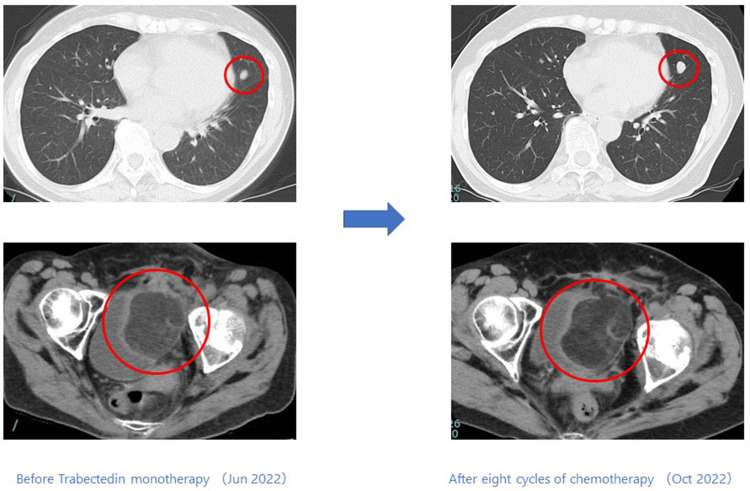

Case presentation: Case 1: A 44-year-old male started trabectedin as second-line therapy after initial chemotherapy, which included doxorubicin. To date, he has completed 9 cycles, showing a response for 6 months. Case 2: A 71-year-old male, deemed intolerant to doxorubicin, started trabectedin as his first-line treatment. He has undergone 50 cycles to date, maintaining a response for 56 months. Case 3: A 59-year-old female began trabectedin as second-line therapy after initial chemotherapy, including doxorubicin. She responded for 6 months before experiencing disease progression. Case 4: A 79-year-old male developed new lesions after one course of initial chemotherapy, including doxorubicin. He then began trabectedin and has maintained a response for 10 months to date.

背景:肌样脂肪肉瘤是一种罕见的肿瘤类型,约占所有脂肪肉瘤的30%。在基础研究和一些临床实验中,携带 FUS/CHOP 融合基因的类粘液性脂肪肉瘤使用曲贝替定取得了良好的效果。然而,曲贝替定对未接受化疗的软组织肉瘤或FUS/CHOP融合基因阳性的肌样脂肪肉瘤的有效性和安全性尚未确定。因此,我们评估了本院四例携带FUS/CHOP融合基因的类粘液性脂肪肉瘤患者接受曲贝替定单药治疗的有效性和安全性:我们分析了在冈山大学接受手术并在川崎医学院接受化疗的四例转移性肌样脂肪肉瘤患者。这些患者的 FUS/CHOP 融合基因检测结果呈阳性,通过 RT-PCR 技术辅助病理诊断。从冷冻肿瘤标本的肿瘤组织切片中提取 RNA。反转录后,使用 TLS/FUS-CHOP 引物进行 PCR。对得到的产物进行电泳,然后确认核苷酸序列:病例 1:一名 44 岁的男性患者在接受了包括多柔比星在内的初始化疗后,开始接受曲贝替定作为二线疗法。迄今为止,他已完成了 9 个周期的化疗,并在 6 个月内出现了反应。病例 2:一名 71 岁的男性患者被认为不能耐受多柔比星,他开始接受曲贝替定作为一线治疗。迄今为止,他已接受了 50 个周期的治疗,56 个月来一直保持着应答。病例 3:一名 59 岁的女性患者在接受了包括多柔比星在内的初始化疗后,开始将曲贝特林作为二线疗法。她在治疗 6 个月后病情出现进展。病例 4:一名 79 岁的男性患者在接受了包括多柔比星在内的一个疗程的初始化疗后出现了新的病变。随后,他开始接受曲贝替定治疗,迄今已有10个月的应答:结论:与其他化疗方法相比,曲贝替丁(Trabectedin)对携带FUS/CHOP融合基因的肌样脂肪肉瘤患者具有潜在的更高疗效和良好的安全性。